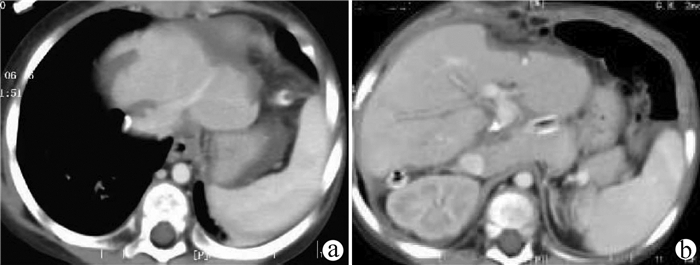

高原地区体外肝切除联合自体肝移植术治疗晚期肝泡型包虫病的术后并发症及其防治策略

田青山, 冯少培, 郭亚民, 韩秀敏, 赵顺云, 叶成杰, 安永德, 吴世乐, 王向前, 郑海波, 朱文君, 阿吉德, 高伟, 潘洪帅

2021, 37(9): 2153-2160. DOI: 10.3969/j.issn.1001-5256.2021.09.029

摘要(1294) HTML (489) PDF (3321KB)(54)

摘要:

目的  探讨高原地区体外肝切除联合自体肝移植术治疗终末期肝泡型包虫病的术后并发症并探讨防治策略。  方法  收集青海省人民医院2013年1月— 2019年3月接受自体肝移植术的11例终末期肝泡型包虫病患者的手术资料及随访资料,对术中及术后情况进行分析。  结果  11例患者均成功行自体肝移植术,无术中死亡,其中2例(18.18%)行半离体肝切除,9例(81.82%)行全离体肝切除。肝后下腔静脉重建方式中,采用自体大隐静脉进行重建者2例(18.18%),采用人造血管重建者4例(36.36%),5例(45.45%)保留自体肝后下腔静脉。胆道重建方式中,8例(72.73%)行胆肠吻合术,3例(27.27%)行胆管端端吻合术。11例患者的术后并发症主要有出血2例(18.18%);胆汁漏、腹腔感染4例(36.36%),胆肠吻合口狭窄1例(9.09%), 血栓2例(18.18%),肺部感染、胸腔积液2例(18.18%);包虫复发1例(9.09%)。11例患者发生围术期死亡2例(18.18%),其余9例(81.82%)患者均好转出院。  结论  出血、胆道并发症和感染是造成高原地区自体肝移植患者死亡的主要原因,精准把握手术适应证、术前仔细多学科评估、术中精湛的操作、外科技术流程的标准化及精细的围术期管理是降低自体肝移植术围术期病死率、避免和减少术后并发症以及使患者获得长期良好生存的关键。